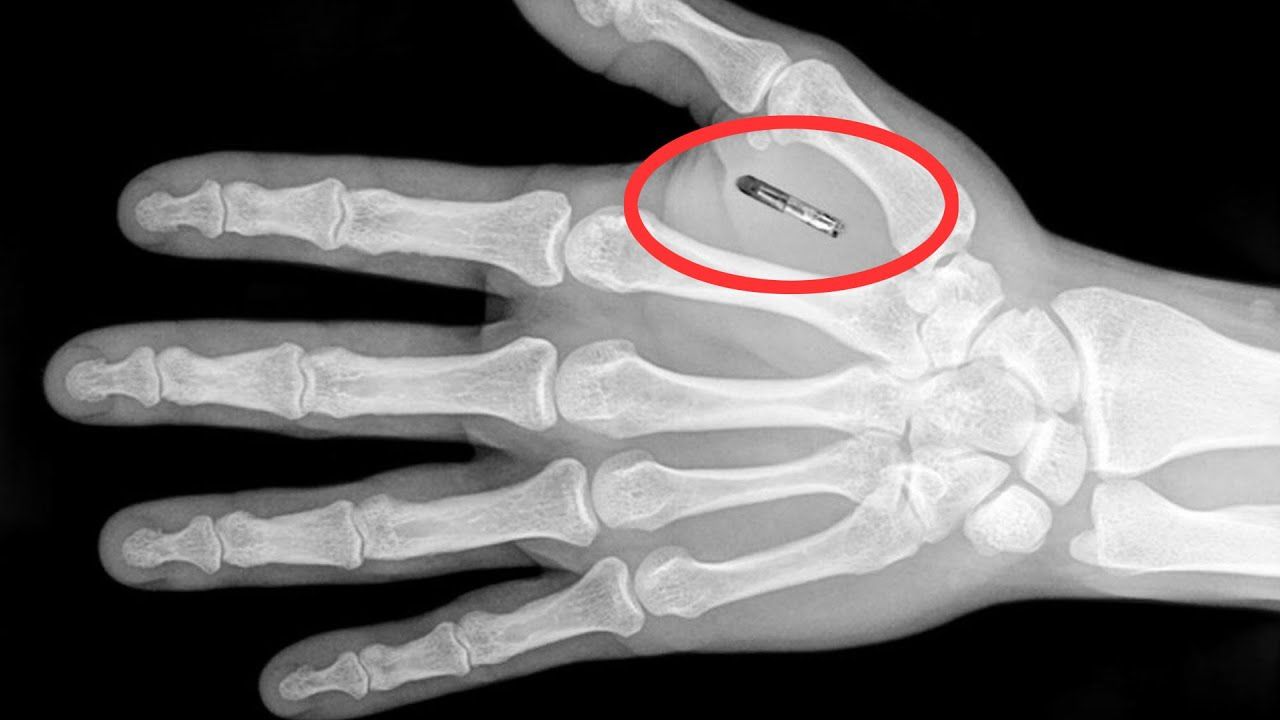

Microchip Trackers Are Being Implanted Via Covid19 Vaccination (Proof?)